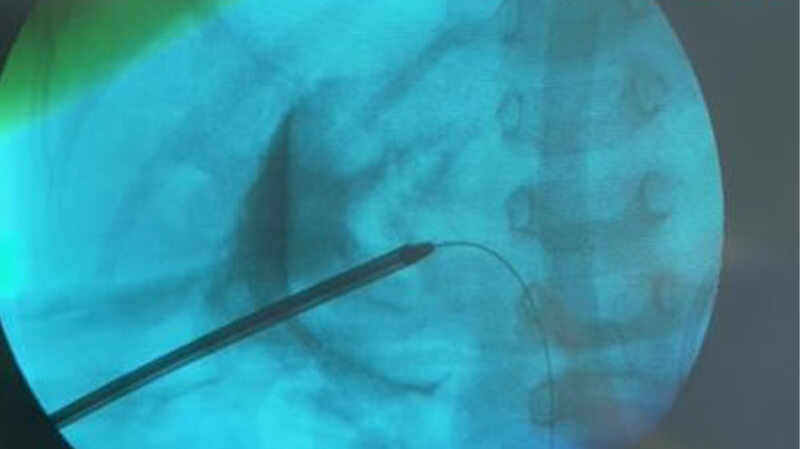

Για την επιτυχή πορεία αυτής της πολύπλοκης και δύσκολης επέμβασης θα ήθελα να ευχαριστήσω όλους όσους, επώνυμα και ανώνυμα, βοήθησαν αλλά κυρίως τους συνεργάτες μου Ουρολόγους, Βασίλη και Νίκο που με στήριξαν σε κάθε βήμα αυτής της περίπλοκης επέμβασης.Παρακάτω οι φωτογραφίες από την ακτινοσκόπηση την ώρα της επέμβασης και η τελική εικόνα με τις νεφροστομίες.